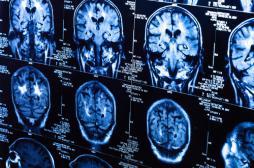

LES MALADIES

SYMPTÔMES